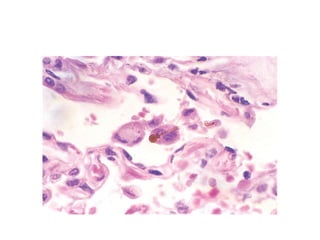

Morphology

• It is difficult to differentiate from other diffuse interstitial

disease unless there is asbestos bodies

• Asbestosis is marked by diffuse pulmonary interstitial fibrosis,

characterized by the presence of asbestos bodies, which are

seen as golden brown, fusiform or beaded rods with a

translucent center.

• They consist of asbestos fibers coated with an iron-containing

proteinaceous material

• Fibrosis begins around the bronchioles & alveolar ducts

• Unlike other forms of pneumoconiosis it affects the lower lobes

• Pleural plaques are the most common manifestations of

asbestosis

• May be complicated by pulmonary HTn & cor pulmonale